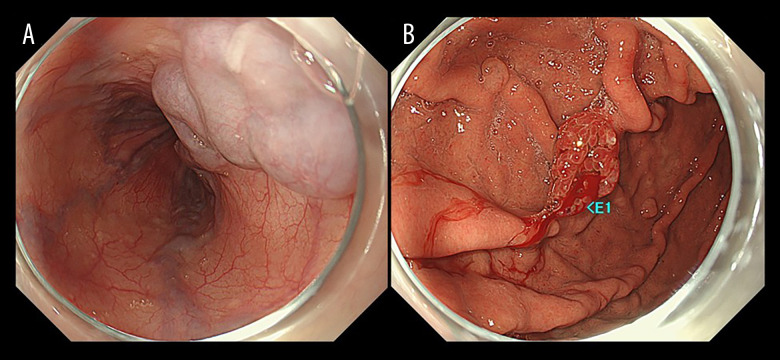

原发性肝神经内分泌肿瘤(PHNENs),包括原发性肝神经内分泌癌(PHNEC),是非常罕见的。尽管混合神经内分泌-非神经内分泌肿瘤预后较差,但PHNENs通常表现为生长缓慢。PHNENs的诊断也具有挑战性。病例报告一名73岁男性接受CT平扫时,偶然发现一个42毫米的孤立性肝脏肿瘤。缺乏维生素K或PIVKA-II诱导的血清蛋白水平升高至138 mAU/mL。13天后,磁共振成像(MRI)显示肝脏肿瘤扩大,肿瘤血栓延伸到肝静脉和门静脉。未观察到早期增强。第18天,多普勒超声和动态CT评估肿瘤为低血管,并出现新的肿胀的孤立淋巴结。第39天,正电子发射断层扫描(PET)/CT显示原发性肝脏肿瘤和转移性淋巴结强烈摄取,并出现其他远处淋巴结转移。第49天,手术切除转移性颈部淋巴结。在第61天,根据组织病理学和免疫组织化学评估明确诊断PHNEC。Ki-67标记指数为90%。在第67天,他住院开始化疗,但CT显示终末期疾病。需要姑息治疗,患者在最初诊断后82天死于癌症。结论:我们报告了一个令人深思的PHNEC病例,肿瘤进展迅速。为了阐明临床意义(例如,非典型影像特征和诊断缺陷),提供了详细的影像结果。我们期望这个病例将对该领域的临床医生提供信息。

BACKGROUND Primary hepatic neuroendocrine neoplasms (PHNENs), including primary hepatic neuroendocrine carcinoma (PHNEC), are extremely rare. PHNENs typically exhibit slow growth, although mixed neuroendocrine-non-neuroendocrine neoplasms have poor prognoses. PHNENs are also challenging to diagnose. CASE REPORT A 73-year-old man underwent plain computed tomography (CT), which incidentally detected a 42-mm solitary hepatic tumor. Serum levels of protein induced by vitamin K absence or antagonist-II (PIVKA-II) were elevated at 138 mAU/mL. Thirteen days later, magnetic resonance imaging (MRI) revealed an enlarged hepatic tumor with tumor thromboses extending into the hepatic and portal veins. No early-phase enhancement was observed. At 18 days, Doppler ultrasound and dynamic CT evaluated the tumor as hypovascular, and a newly swollen solitary lymph node appeared. At 39 days, positron emission tomography (PET)/CT revealed strong uptake in the primary liver tumor and metastatic lymph nodes, with additional distant lymph node metastases emerging. At 49 days, a metastatic cervical lymph node was surgically resected. At 61 days, PHNEC was definitively diagnosed based on histopathological and immunohistochemical assessments. The Ki-67 labeling index was >90%. At 67 days, he was hospitalized to begin chemotherapy, but CT revealed end-stage disease. Palliative treatment was required, and the patient died of cancer 82 days after the initial diagnosis. CONCLUSIONS We have presented a thought-provoking case of PHNEC with rapid oncological progression. To clarify clinical implications (eg, atypical imaging features and diagnostic pitfalls), detailed imaging findings are provided. We anticipate that this case will be informative for clinicians in this field.